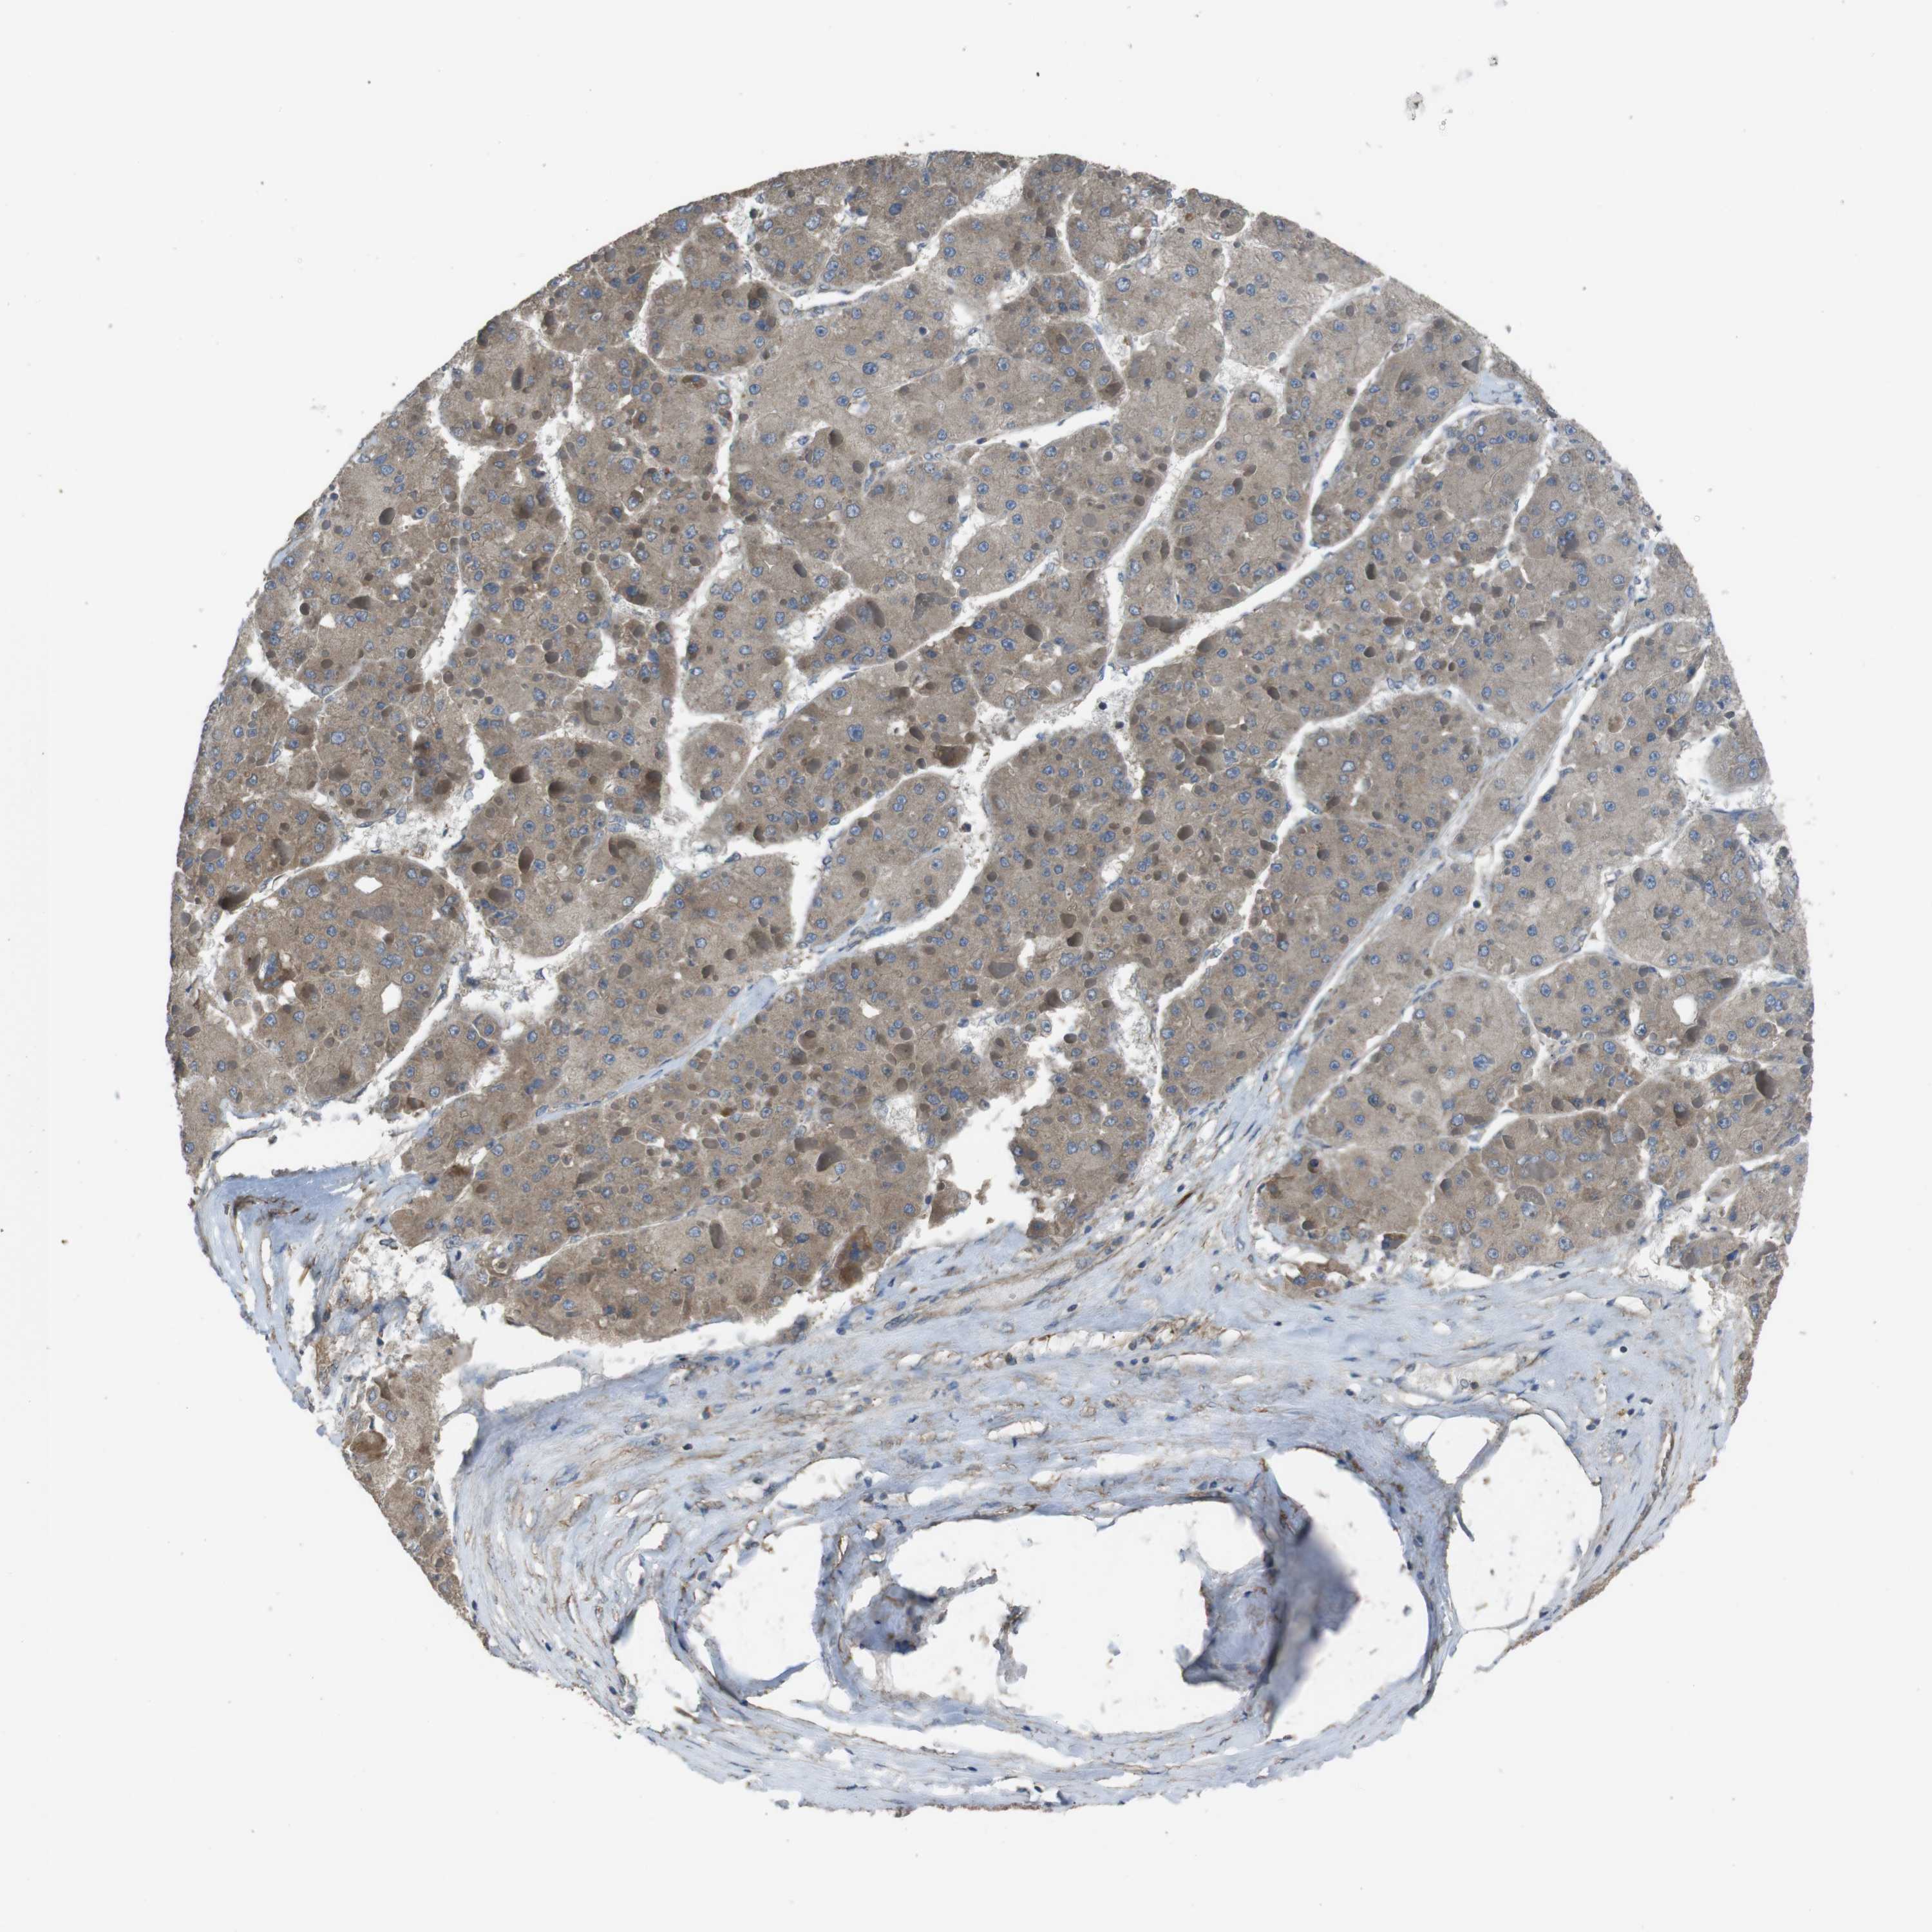

LIVER CANCER - Protein expressioni

A mouse-over function shows sample information and annotation data. Click on an image to view it in a full screen mode. Samples can be filtered based on level of antibody staining by selecting one or several of the following categories: high, medium, low and not detected. The assay and annotation is described here.

Note that samples used for immunohistochemistry by the Human Protein Atlas do not correspond to samples in the TCGA dataset.

Antibody stainingi

Antibody staining in the annotated cell types in the current human tissue is reported as not detected, low, medium, or high, based on conventional immunohistochemistry profiling in selected tissues. This score is based on the combination of the staining intensity and fraction of stained cells.

Each image is clickable and will lead to virtual microscopy that enables deeper exploration of all samples and also displays staining intensity scores, fraction scores and subcellular localization as well as patient and tissue information for each sample.

Antibody HPA014402

Staining

High

Medium

Low

Not detected

Intensity

Strong

Moderate

Weak

Negative

Quantity

>75%

75%-25%

<25%

None

Location

Nuclear

Cytoplasmic/membranous

Cytoplasmic/membranous,nuclear

Cholangiocarcinoma

Carcinoma, Hepatocellular, NOS